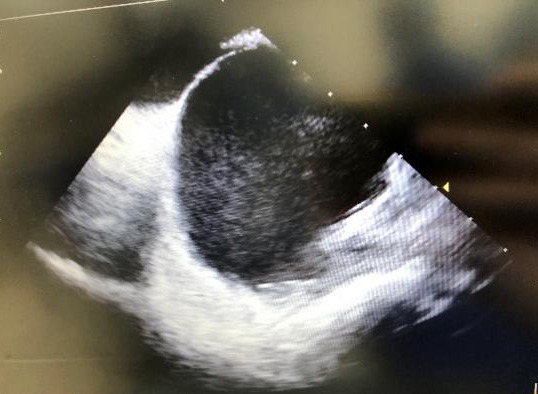

▲ICE下卵圆孔未闭

3月8日,手术如期进行。富丽娟为患者实施局部麻醉穿刺双侧股静脉,皮林带领团队运用心腔内超声(ICE),将只有三个多毫米直径的微小超声波探头,通过股静脉直接送到心脏内部,心房、卵圆窝、心耳等结构通过ICE成像实时清晰可见。包恩泽在ICE的直视和引导下,顺利将导管精准通过卵圆孔未闭处,释放封堵伞,完美封堵缺口,再次通过ICE观察和验证没有分流,手术圆满结束。本次手术在ICE实时监控下,从穿刺到手术成功历时不到30分钟。患者王女士于术后安返病房,并于术后第3天顺利出院。